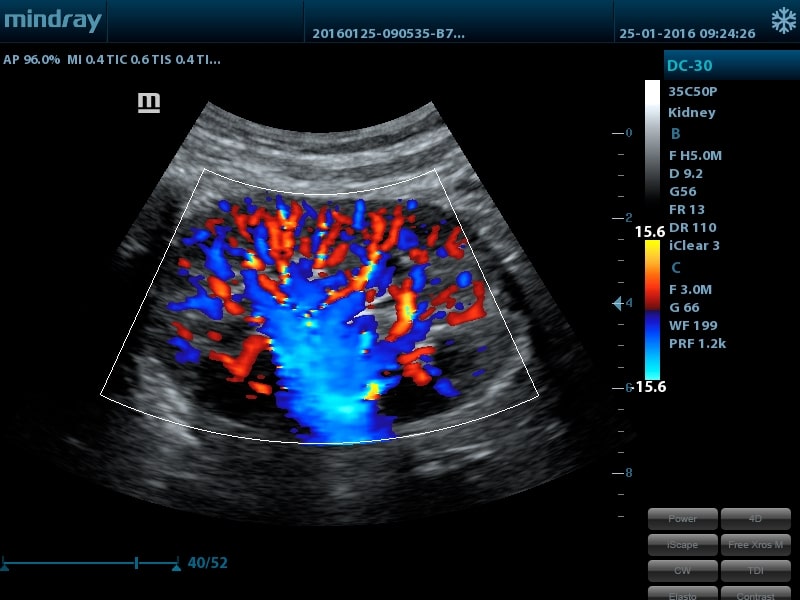

- UWN Contrast Imaging™ - опция нелинейной визуализации в ультрашироком диапазоне для проведения обследования с применением контрастных веществ (поддерживается на датчике 35С50Р)

- Конвексный датчик 35C50P, 1,8 - 6,0 МГц, R50мм, 80 элементов